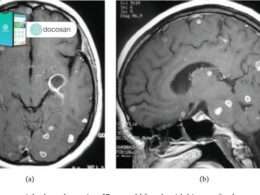

Đôi khi, các phương pháp chẩn đoán hình ảnh (như chụp X-quang, siêu âm hoặc chụp CT) có thể cho hình ảnh gợi ý ổ giun trong các cơ quan ở bụng hoặc ngực.